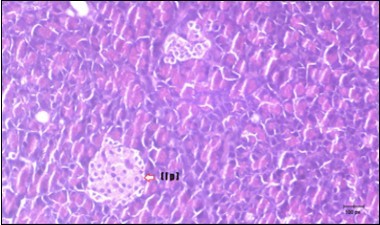

Pancreas Histopathological Observations

Histological examination of pancreas of the control rats showed normal sized islets of pancreas (Ip) compared to the diabetic rats which showed markedly atrophic islets of pancreas (I.p.) (Figure 8 and Figure 9). Pancreas of in groups (3) and (4) rats showed mild atrophic islets of pancreas (I.p.) with inflammatory cellular infiltrate (Figure 10 and Figure 11). The pancreas of rats in group (5) showed nearly normal islets of pancreas (I.p.) with few inflammatory cellular infiltrate (I.c.) (Figure 12).

Figure 9.Photomicrogragh of pancreas section of diabetic rat showing the markedly atrophic islets of Langerhans. (arrow) (H&E) (40X).

Figure 11.Photomicrogragh of pancreas section of treated rat with Glimepiride showing mildly improved of isled of Langerhans with large number of cells (dashed-arrow). (H&E) (40X).